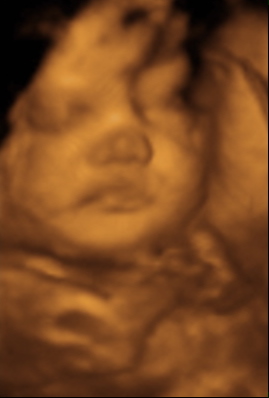

35 week Ultrasound

Friday, July 2nd, 2010

She weighs 5 pounds (2.25kg) and we think she’s pretty cute.